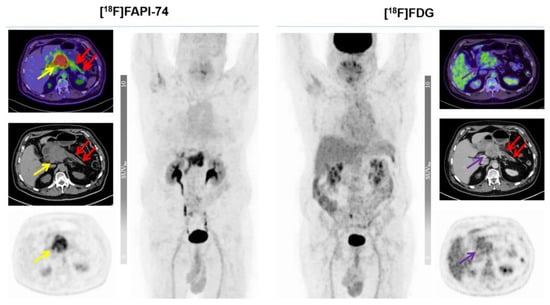

3.3. [18F]FAPI-74 Uptake in Tumor Lesions

3.4. [18F]FAPI-74 in PDAC with Confounding Pancreatitis